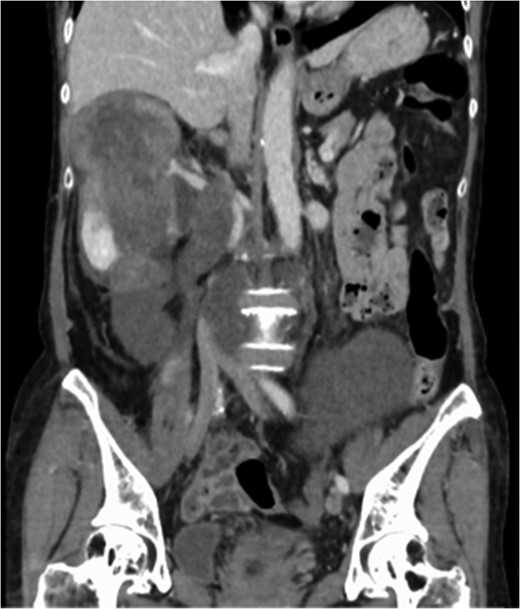

A 60-year-old female visited a clinic because of abdominal distension. She noticed abdominal distention one year prior to her clinical visit, but she left it for a year. Gradual enlargement of the mass eventually made her decide to see a doctor. Enhanced abdominal computed tomography (CT) revealed large retroperitoneal tumors. Mini-laparotomy and tumor biopsy confirmed her diagnosis as dedifferentiated liposarcoma, then she was referred to us for further examination and treatment. A multidetector CT scan revealed a hypodense mass in the retroperitoneum, with a size of ~30 × 20 cm2. The tumor appeared to invade the duodenum, head of the pancreas, right kidney, IVC and abdominal aorta (Fig. 1). The IVC was almost occluded by the tumor, but venous return from the lower extremities beyond the tumor was observed through collateral veins around the tumor (Fig. 2). The tumor invaded the abdominal aorta just below the left renal artery to the common iliac artery bifurcation, although the root and entire length of SMA appeared to be free from the tumor (Fig. 3). She underwent en bloc resection of the RL with resection of the right kidney, duodenum, head of the pancreas, a portion of the inferior IVC and abdominal aorta. Ax-F & F-F bypass was performed for vascular reconstruction using poly-tertrafluoroethylene (PTFE) to maintain the blood flow to the both lower extremities (Fig. 4). The lower abdominal aorta and both sides of common iliac arteries were resected with the tumor. The proximal stump of the abdominal aorta was closed with a running suture and covered by the omentum. The IVC was resected from just below the left renal vein to the common iliac veins. Reconstruction of the venous system including IVC and common iliac veins was not performed because venous collateral pathways had already developed sufficiently. Child’s reconstruction was performed after pylorus-preserving pancreatoduodenectomy. The duration of the surgery was 19 h 22 min, and blood loss was 4 811 mL, requiring 1680 mL of red blood cell transfusion. The tumor was 33 × 20 × 13 cm3 in size, weighed 4800 g, and had a fibrous capsule (Figs 5 and 6). Pathological examination revealed a dedifferentiated liposarcoma with negative margin (Fig. 7). Tumor invaded the pancreatic capsule, the renal capsule, the adventitia of the IVC and the abdominal aorta and infiltrated into the muscularis propria and focally into lamina propria of the duodenum. Edema of the both lower extremities was noted as postoperative complication, but that was gradually resolved by diuretics. The patient was discharged 37 days after surgery without serious postoperative complications such as pancreatic fistula, as well as graft infection or obstruction of two bypasses. Currently, she remains alive and well with no evidence of recurrence at 16 months post-operation.

Multidetector CT scan (coronal view and sagittal view). The tumor surrounded the abdominal aorta from the superior mesenteric artery orifice to the common iliac artery bifurcation.